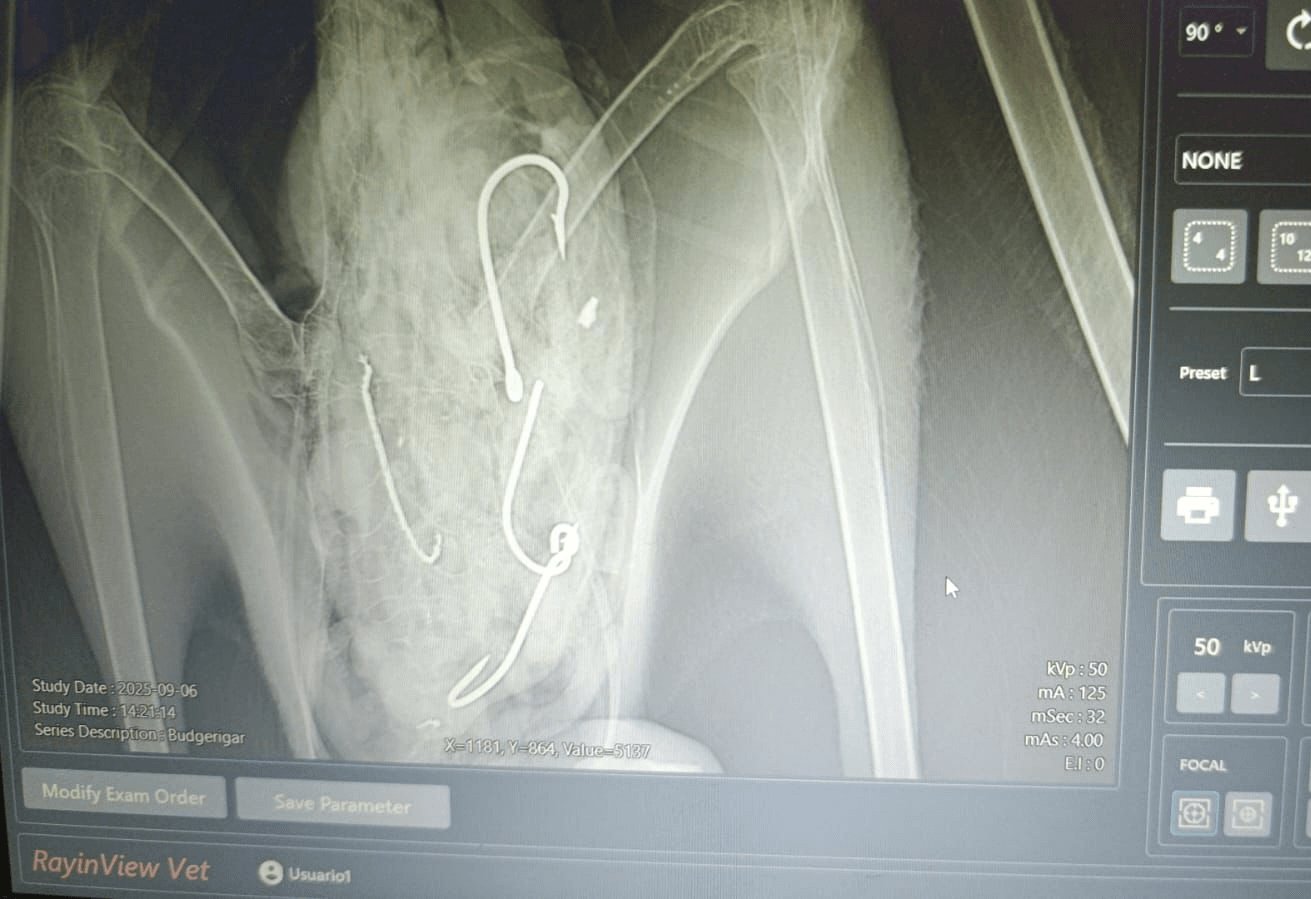

Vzácný mořský pták se zotavuje z úspěšné a život zachraňující operace. Rybář z Anconcito v Ekvádoru našel mládě Salvinova albatrosa poté, co si všiml, že mu není dobře. Pták pozřel čtyři velké rybářské háčky a několik vlasců a byl převezen do Puerto Lopez k rehabilitaci a péči. Místní veterinář Ruben Aleman ptákovi odstranil vyřazené rybářské vybavení. Po nějakém zvláštním výzkumu a výzkumu byl pták vypuštěn na konci října na nedaleké pláži v provincii Manabí.

„Prostřednictvím koordinace s místním zástupcem ekvádorského ministerstva životního prostředí (REMACOPSE) a specializovaným veterinářem jsme ptákovi úspěšně odstranili čtyři rybářské háčky, včetně jednoho, který způsobil poranění jícnu,“ uvedl v prohlášení Giovanny Suárez Espín, koordinátor ekvádorských vedlejších úlovků mořských ptáků pro American Bird Conservancy.

„Typ a velikost háčků naznačují, že pocházejí z řemeslného rybolovu mahi-mahi, který představuje riziko pro albatrosy. I když je snižování vedlejších úlovků při tomto typu rybolovu náročné, nadále prosazujeme osvědčené postupy a udržitelnější nástroje k minimalizaci náhodného odchytu mořských ptáků.“